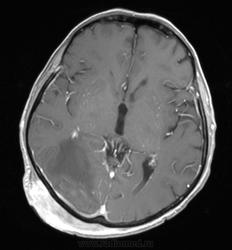

Мужчина проходит курс химиотерапии по поводу Т-клеточной лимфомы с первичным поражением кишечника (гистологическая верификация). За последний месяц - появление множественных очагов в печени, а также необычных изменений в голове.

- бесформенное образование в мягких тканях затылочной области, накапливающее контраст;

- утолщение твердой мозговой оболочки в той же области с накоплением контраста по пахименингиальному типу;

- отек прилежащей мозговой ткани с геморрагическими изменениями в коре, сопровождающийся масс-эффектом.

Мое мнение это лимфома кожи с прорастанием (если так можно сказать) через перфорирующие сосуды в ТМО, с кровоизлияниями в коре за счет повреждения сосудов. Либо это лептоменингальнаые проявления лимфомы. Больше на ум ние чего не приходит. Хотелось бы услышать мнение более опытных специалистов. но все почему-то молчат...

Я тоже думаю, что это лимфома. Думаю, не так важно, прорастает ли она из мягких тканей в мозговые оболочки, или наоборот. Только поражение мозговой оболочки - это пахи-, а не лептоменингиальные изменения.

В таком случае изменения в мозговой ткани - это отек, обусловленный нарушением венозного оттока по поверхностным венам; думаю, вкупе с геморрагическими изменениями этот отек можно квалифицировать как венозный инфаркт.